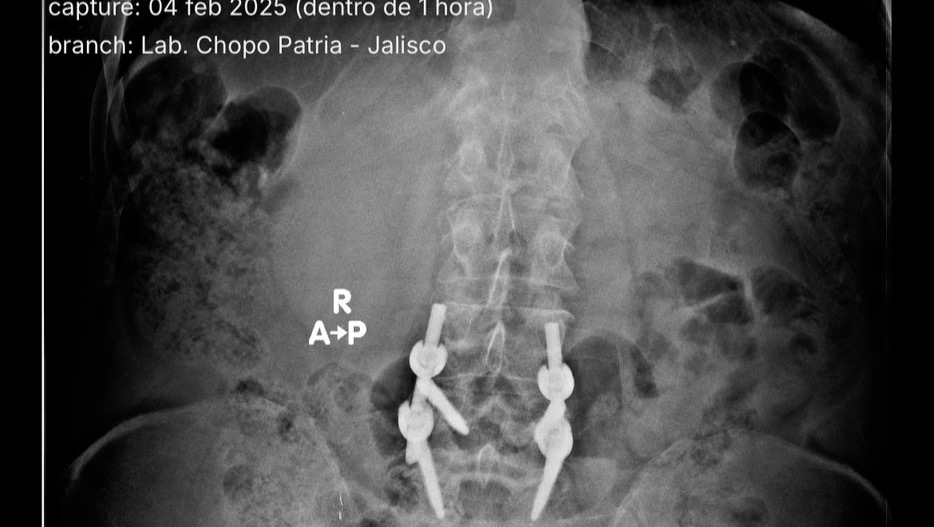

Es extremadamente raro que los tornillos se rompan todos. Se puede romper uno, o dos, pero cuatro es un caso especial y preocupante.

Él fue operado por la Seguridad Social en Agosto de 2019, pero sufrió una caída catastrófica en Mayo de 2021, donde el implante que le fue puesto, sufrió la rotura de todos los tornillos de titanio que le habían colocado (cuatro), con lo que la placa que los unía, quedó flotando. Esto le ha provocado mucho dolor y complicaciones, llegando incluso a no poder caminar, y esto se ha agravado en los últimos días.

Es necesario, por supuesto, colocar nuevos tornillos, en esta ocasión 8 de ellos, más otros elementos necesarios, como placa y un puente que los una. Además, nos indico la necesidad de donaciones de sangre +B, de la que nos haremos cargo nosotros, que tenemos la misma sangre que nuestro Papá.